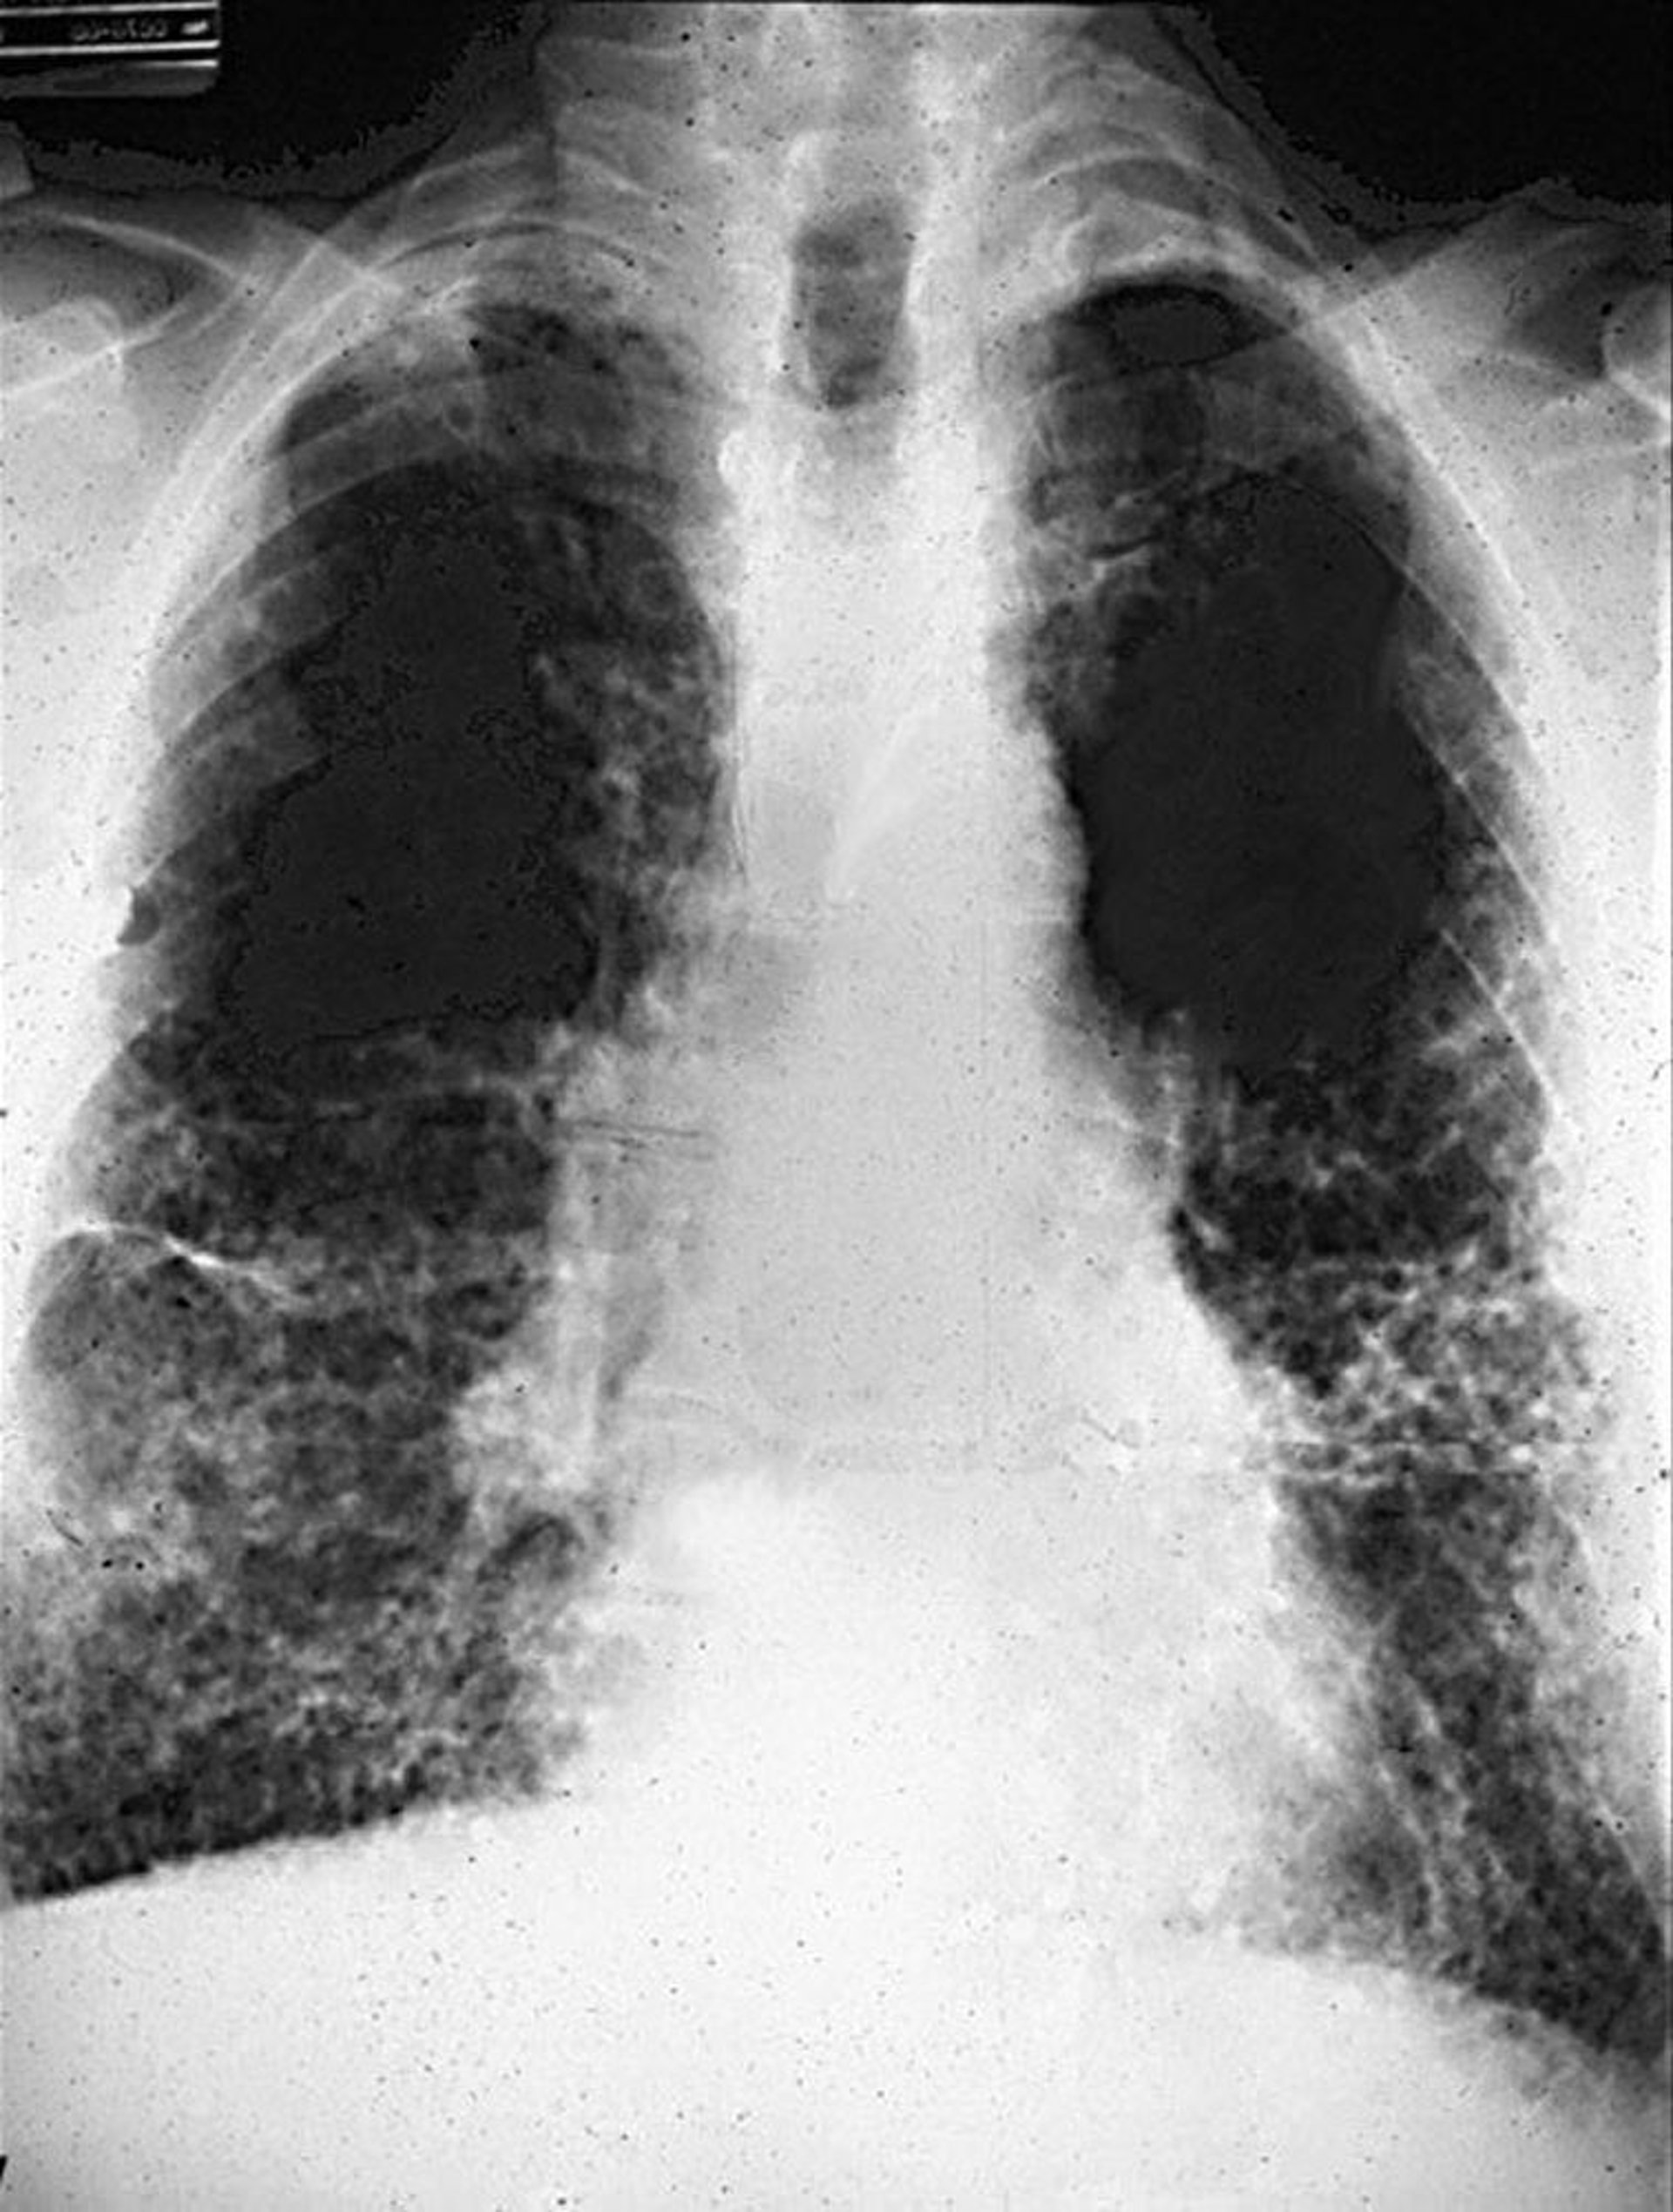

Ретикулярные изменения с ячеистой структурой при асбестозе.

Image courtesy of David W. Cugell, MD.